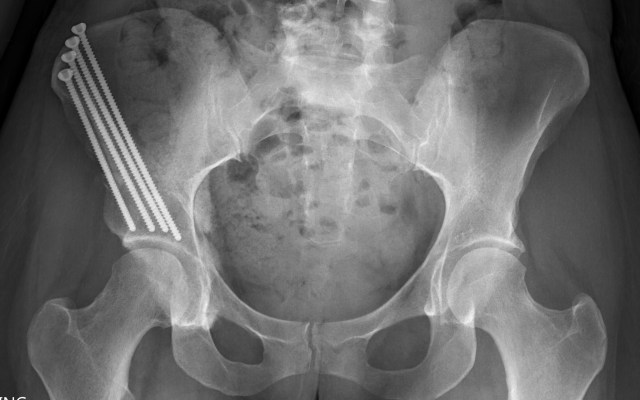

I ventured out once in the rain. I had PT and also needed to get follow up x-rays taken to make sure everything still looks good. All is well and my screws are still in place!